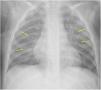

The World Health Organization defines the multisystem inflammatory syndrome in children (MIS-C) as a new syndrome reported in patients aged <19 years old who have a history of exposure to SARS-CoV-2. The onset of this syndrome is characterized by persistent fever that is associated with lethargy, abdominal pain, vomiting and/or diarrhea, and, less frequently, rash and conjunctivitis. The course and severity of the signs and symptoms vary; in some children, MIS-C worsens rapidly and can lead to hypotension, cariogenic shock, or even damage to multiple organs. The characteristic laboratory findings are elevated markers of inflammation and heart dysfunction. The most common radiological findings are cardiomegaly, pleural effusion, signs of heart failure, ascites, and inflammatory changes in the right iliac fossa. In the context of the current COVID-19 pandemic, radiologists need to know the clinical, laboratory, and radiological characteristics of this syndrome to ensure the correct diagnosis.

El síndrome inflamatorio multisistémico pediátrico vinculado a la COVID-19 (SIM-PedS) es, según la Organización Mundial de la Salud, un nuevo síndrome descrito en pacientes menores de 19 años con historia previa de exposición a SARS-CoV-2. La presentación inicial de este síndrome se caracteriza por fiebre persistente que asocia debilidad, dolor abdominal, vómitos y/o diarrea. Menos frecuentemente los pacientes pueden presentar también erupción cutánea y conjuntivitis. El cuadro clínico tiene expresividad y evolución variables, por lo que algunos pacientes pediátricos afectados pueden empeorar rápidamente, desarrollando desde hipotensión y shock cardiogénico a daño multiorgánico. Los hallazgos analíticos característicos del síndrome consisten en elevación de marcadores inflamatorios y disfunción cardíaca. Los hallazgos radiológicos más frecuentes son cardiomegalia, derrame pleural, signos de insuficiencia cardíaca, ascitis y cambios inflamatorios en la fosa ilíaca derecha. En la pandemia actual por COVID-19 es necesario que el radiólogo conozca las características clínico-analíticas y radiológicas de este síndrome para realizar un correcto diagnóstico.